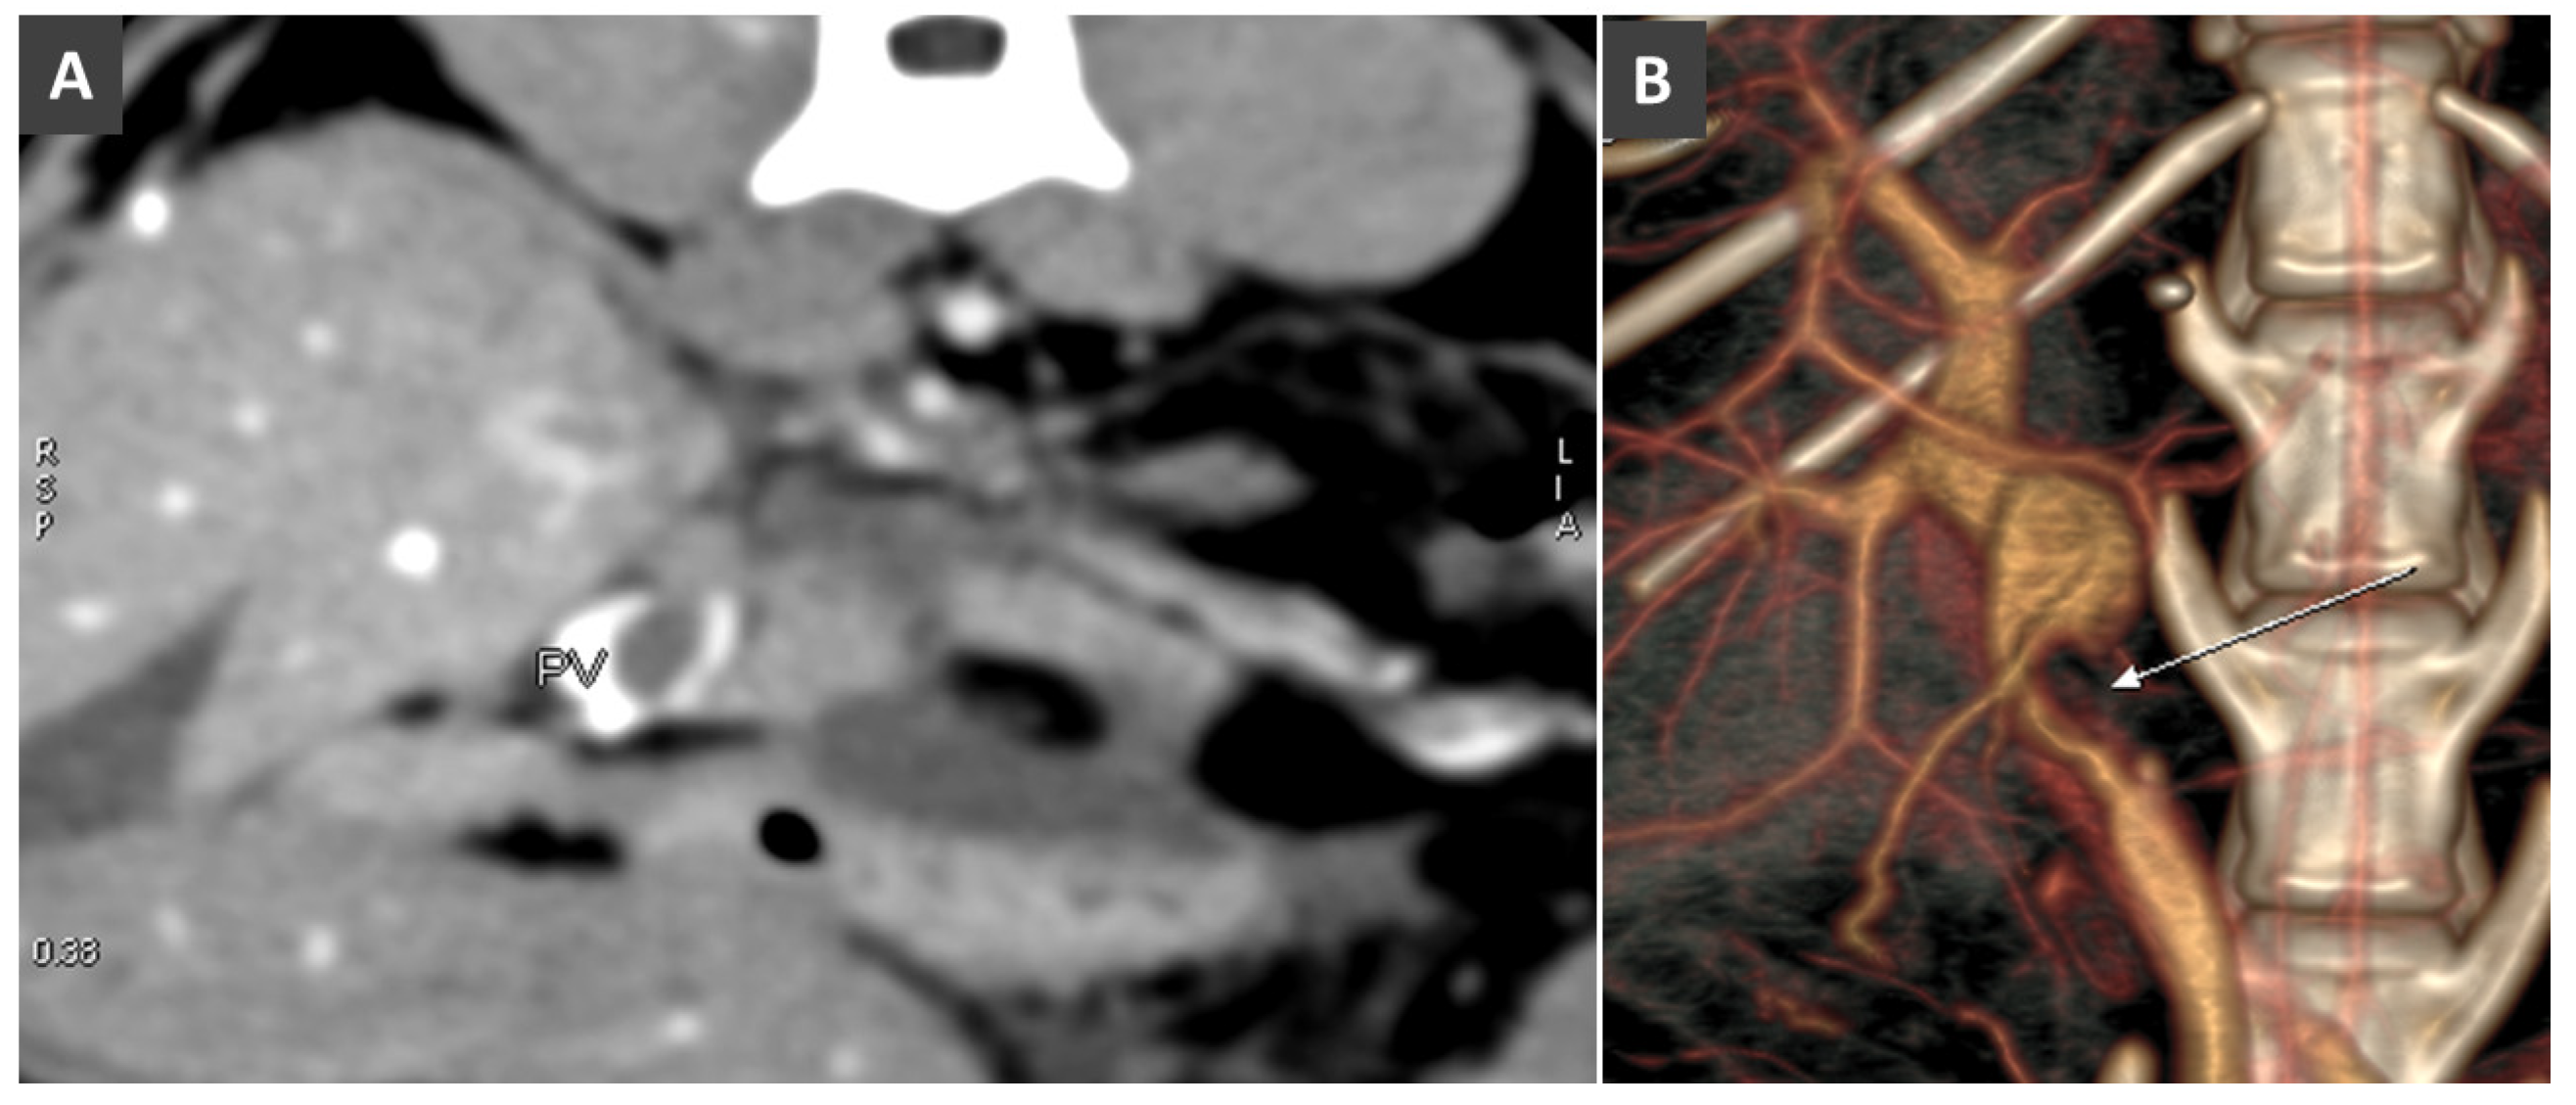

- Bertolini, G.; Caldin, M. Computed tomography findings in portal vein aneurysm of dogs. Vet. J. 2012, 193, 475–480. [Google Scholar] [CrossRef] [PubMed]

- Miyawaki, S.; Washizu, M.; Maeda, S.; Shibata, S.; Watanabe, K.; Yamazoe, K. Portal vein aneurysm in a dog. J. Vet. Med. Sci. 2012, 74, 1191–1193. [Google Scholar] [CrossRef] [PubMed]